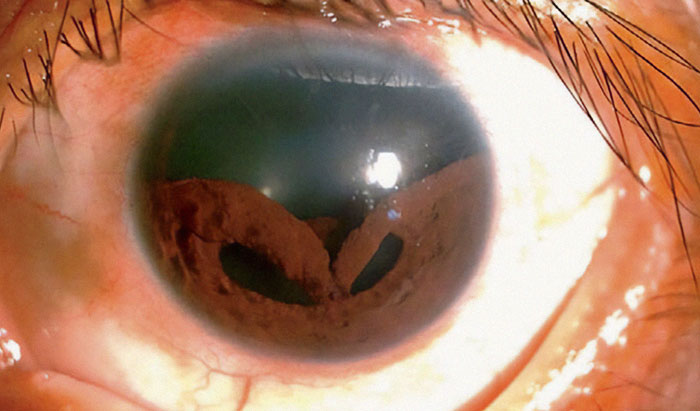

Bungee Cord To The Eye Caused Man's Iris To Collapse Into Multiple Deformed Pupils

@eye surgeon Bored Pandas: is this, umm, repairable? What does he see?